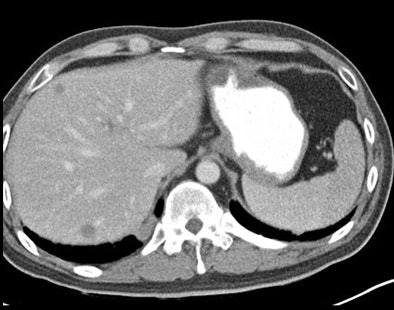

| Hypovascular liver lesions at DSCT are more conspicuous at 80 kVp (top) than at weighted-average data simulating 120 kVp. Images courtesy of Dr. Michael Macari. |

The mean size of the metastases was 2.6 cm. The mean standard deviation of the attenuation difference between the metastases and the normal liver at 80 kVp was 72.3 ± 27 HU at 80 kVp versus 54.2 ± 18.7 at 120 kVp. The mean attenuation difference was significantly higher at 80 kVp (p < 0.001). In two cases, metastases were detected only at 80 kVp.

"We also noted that the attenuation of the normal liver was greater at 80 kVp [132.1 ± 19.6 HU] than at 120 kVp [100 ± 14.3 HU], and it's this difference in the attenuation of the normal liver that really tells you the difference between normal liver and the metastasis," Macari said.

The contrast-to-noise ratio was greater at 80 kVp even though these are noisier images, because the contrast is so much greater.